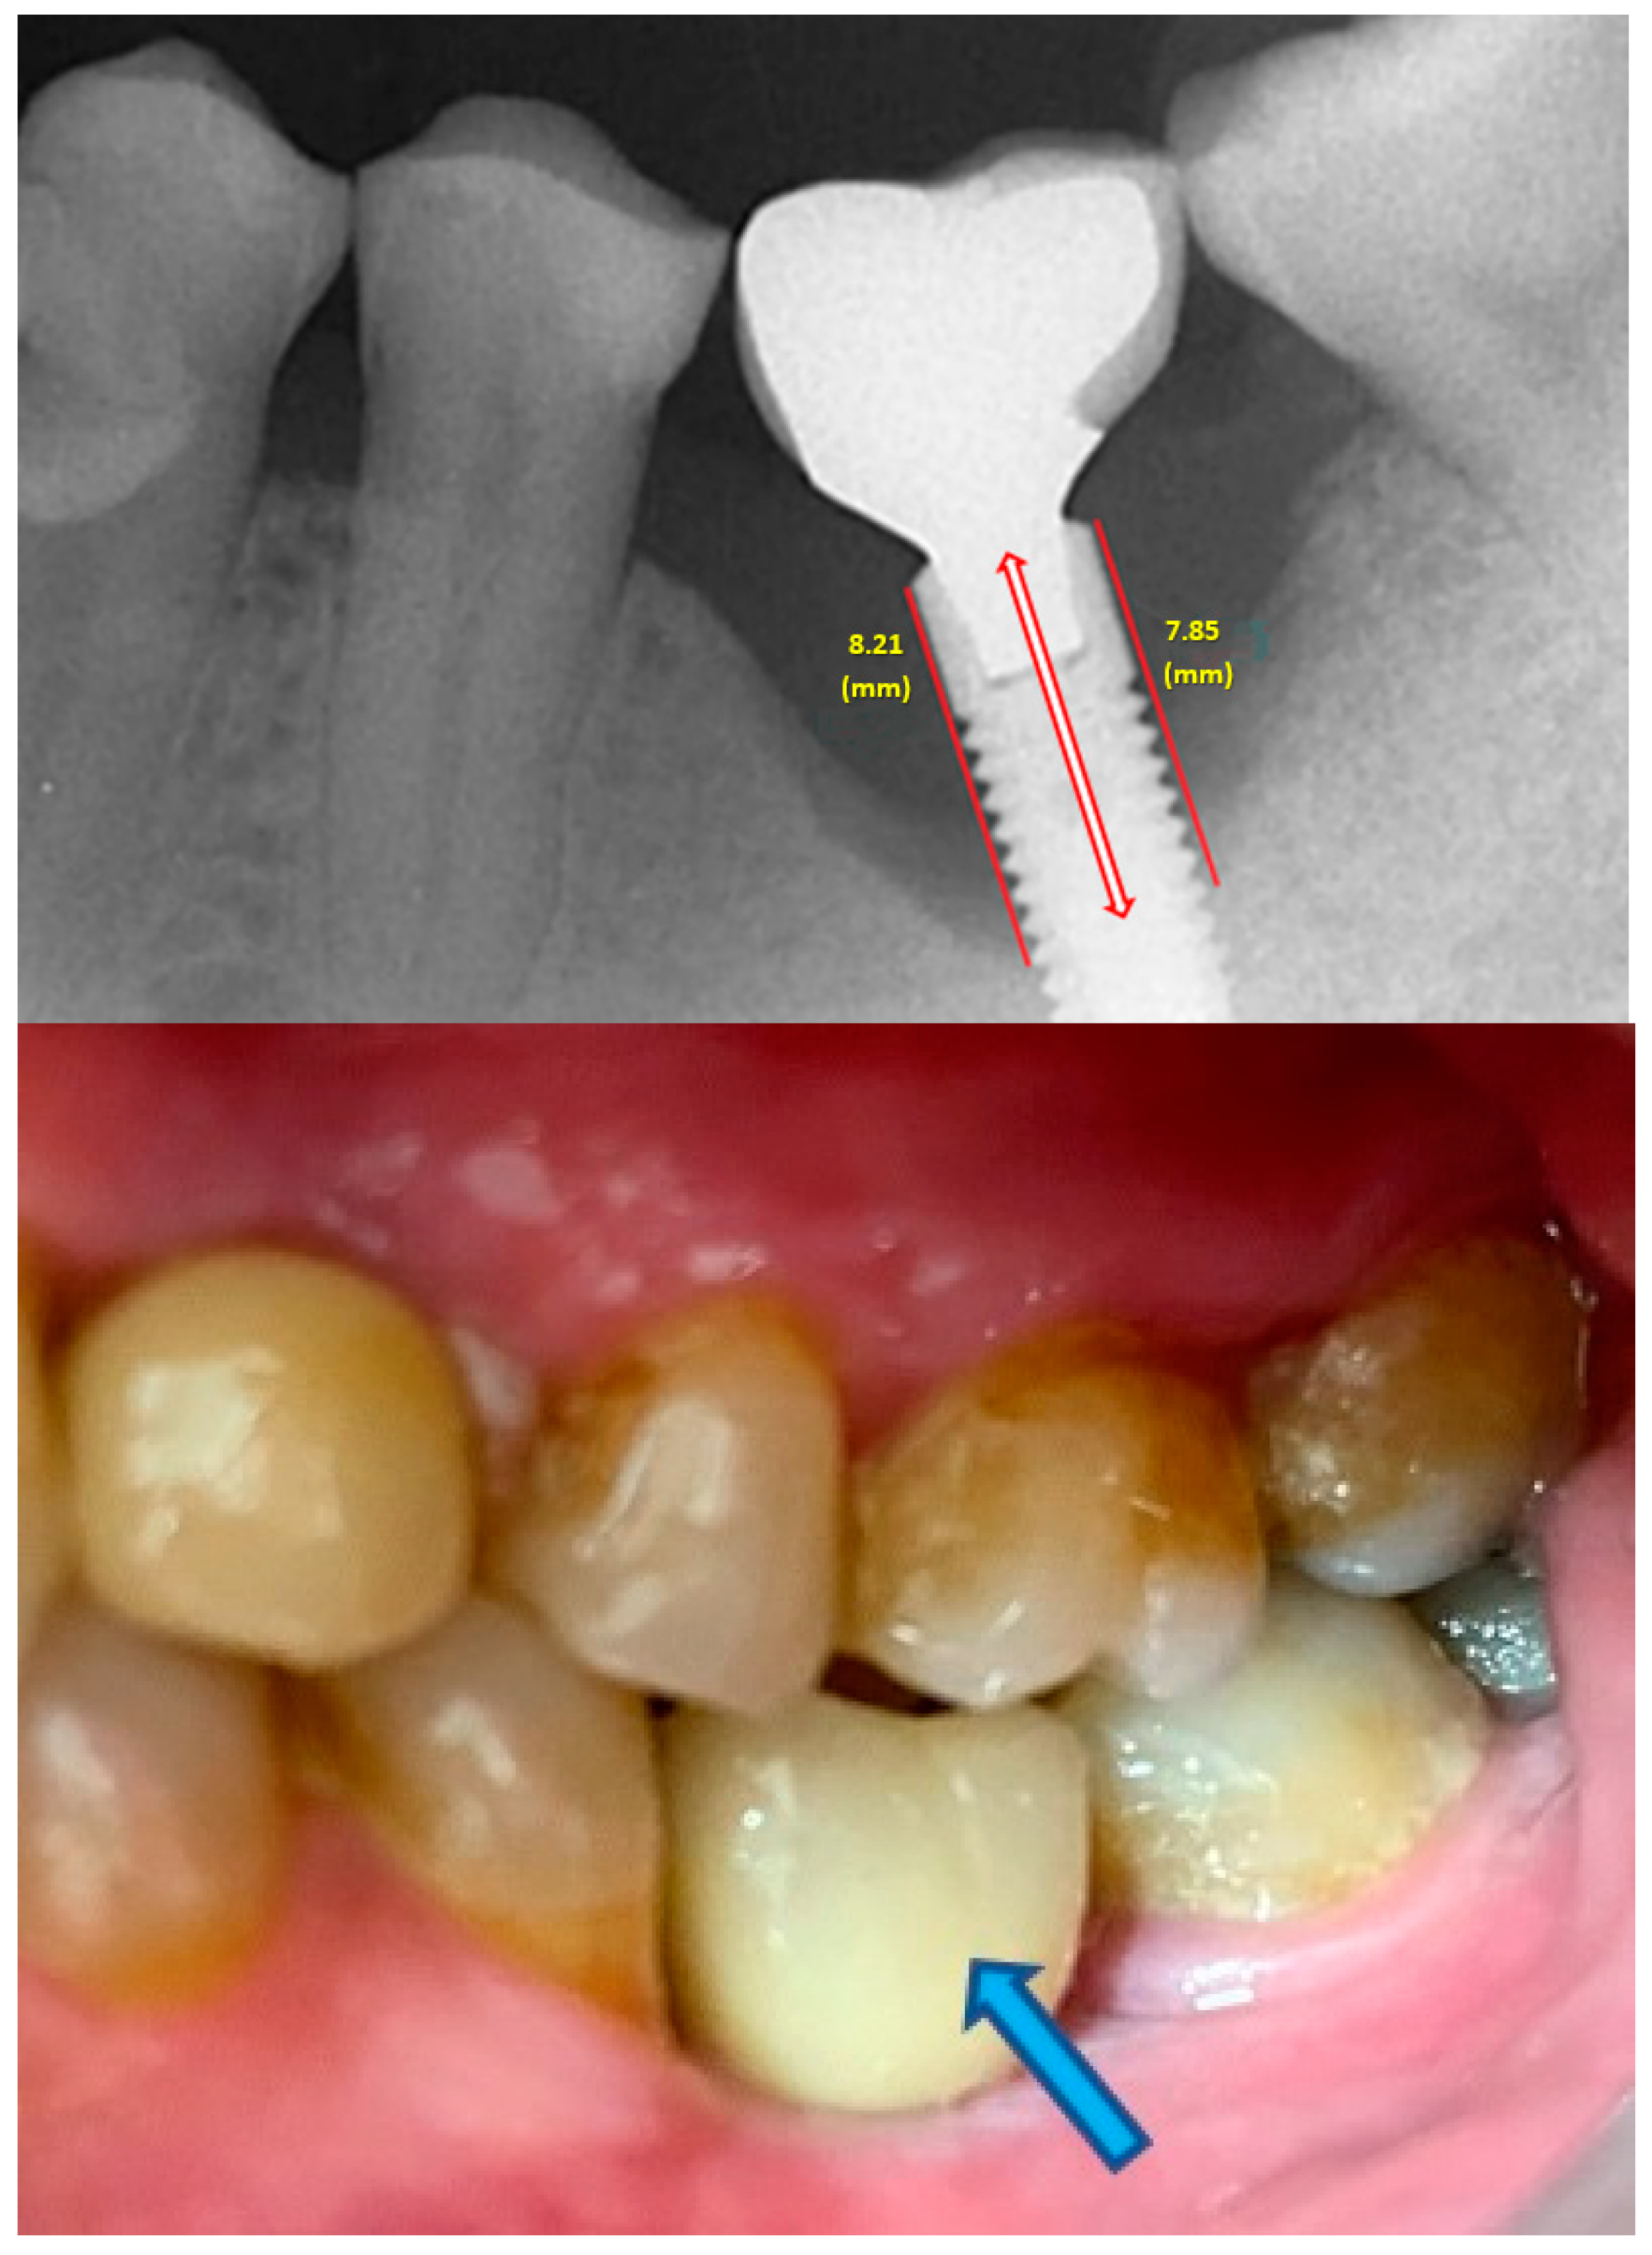

- Measurement of mesial and distal bone loss: Clinically, an increase in the probing depth of the peri-implant pockets, both mesial and distal, was recorded using a calibrated probe with a force of 0.25 N. Radiographically, mesial and distal peri-implant bone height loss was measured using properly performed radiological projections. In fewer than five patients, statistically significant findings in cases of bone loss were difficult to achieve.

- Measurement of the mesial and distal cantilever: The mesial cantilever was significantly greater for the bilateral bone loss group (1833.5 ± 1531.4 µm) compared to the group without MBL (1029.5 ± 968.6 µm) (F = 2.77; p < 0.05). Concerning the effect of the mesial versus distal cantilever, although the mesial cantilever appears to be more favorable, the only article found in the literature regarding this finding is a study by Romeo et al. (2003), which showed that this effect is not always consistent, although the difference is minimal [31].